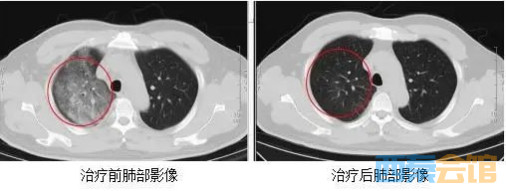

发热门诊医生详细询问顾先生的既往病史,并为其进行细致的体格检查。胸部CT结果显示,顾先生的双肺存在大面积的炎症病变

鉴于顾先生的肺部感染情况较为严重,门诊医生立即将其收住感染科病房接受进一步治疗。

在感染科医护团队的精心治疗与细致护理下,顾先生的发热、咳嗽、胸闷等症状逐渐缓解。复查的CT结果显示,肺部炎症情况得到了明显的改善。目前,顾先生已经顺利康复出院。